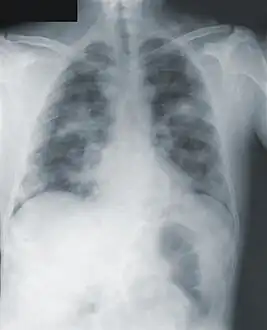

Chest x-ray of pneumonic plague showing bilateral, diffuse interstitial pleural infiltrates, and accompanying consolidation. As well as, what appeared to be marked, mediastinal adenopathy.